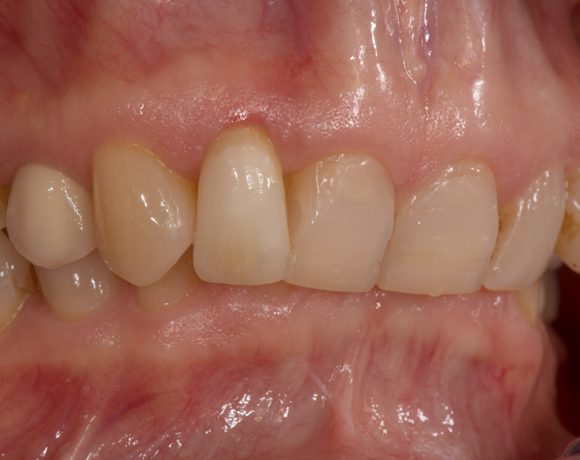

Zeramex T Implantat für Zahn 22

Einzelimplantate in der Front stellen oft ein Problem dar. Zirkonimplantate im Gegensatz zu Titanimplantate machen ästhetisch weniger Probleme, durch die weisse Farbe passen sie sich besser an das Zahnfleisch an.

Ein Projekt aus dem Jahr 2013

Im vorliegenden Patientenfall musste der Zahn 22 nach erfolgloser Endodontie entfernt werden. Die Nachbarzähne waren kariesfrei, es wurde eine Marylandbrücke (eine Brücke mit zwei Flügelchen, die palatinal an den Nachbarzähnen verklebt werden) oder ein Implantat besprochen. Die Patientin hat sich für ein Vollkeramikimplantat entschieden. In der Diashow wird der operative Eingriff bis zur fertigen Krone gezeigt. Die Einheilzeit betrug drei Monate.